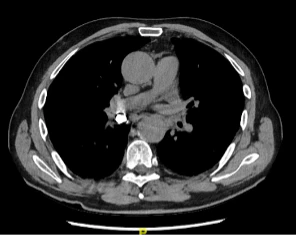

Un patient de 60 ans développe une dyspnée aiguë quelques heures après s’être rendu chez le dentiste. Il rapporte avoir subit plusieurs extractions dentaires et lors du moment du décompte des dents enlevées, il en manquait une. Le dentiste a conclu que le patient avait dû l’avaler. Par la suite, le patient présente une gêne thoracique motivant sa consultation aux urgences.

Le CT-scan thoracique, dont on voit ici le scout, met en évidence une structure hyperdense, de densité métallique, au sein de la bronche intermédiaire droite, pouvant correspondre à une couronne dentaire métallique, sans signe d’occlusion complète de la bronche. L’évolution est favorable après récupération de la dent logée dans la bronche intermédiaire droite par bronchoscopie.